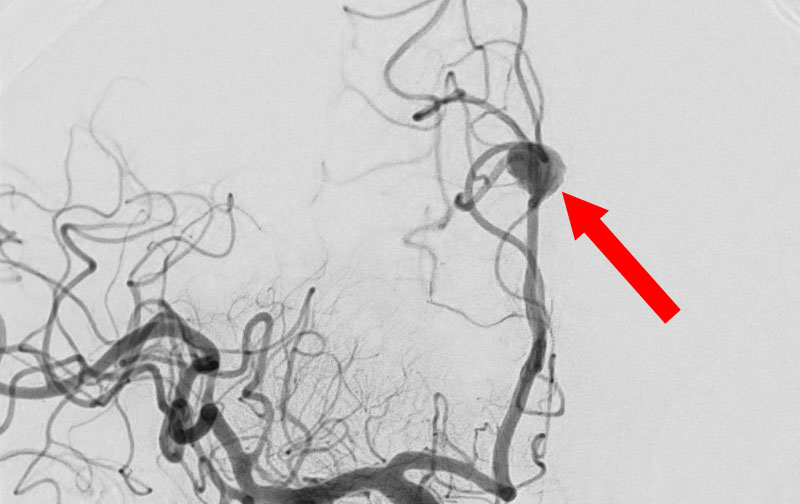

No.1595 手術前